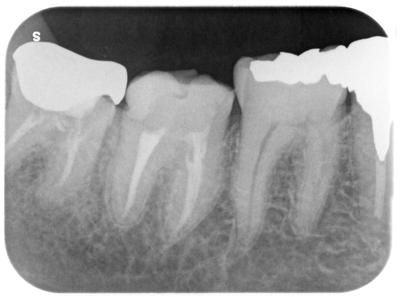

2週間後再来院、根管充填完了。

前回治療の翌日には1ヶ月以上続いた痛みもとれたらしい。

術後